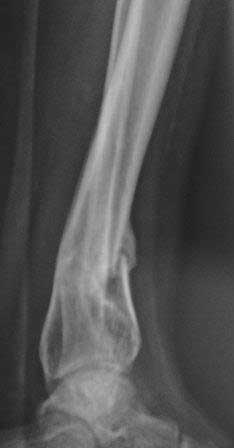

Cегодня больная оперирована, удалось произвести закрытую остеоклазию обеих костей, одномоментно устранить рекурвацию голени, фиксация аппаратом Илизарова из трех колец (II, V, VIII), дистально тремя спицами. Завтра выложу рентген.снимки.

Р-снимки после закрытой остеоклазии и коррекции деформации, а также после фиксации аппаратом, дистальные спицы прошли близко к линии излома но фиксация стабильная, деформация клинически исчезла,

больная довольна, начала ходит дозированной нагрузкой.